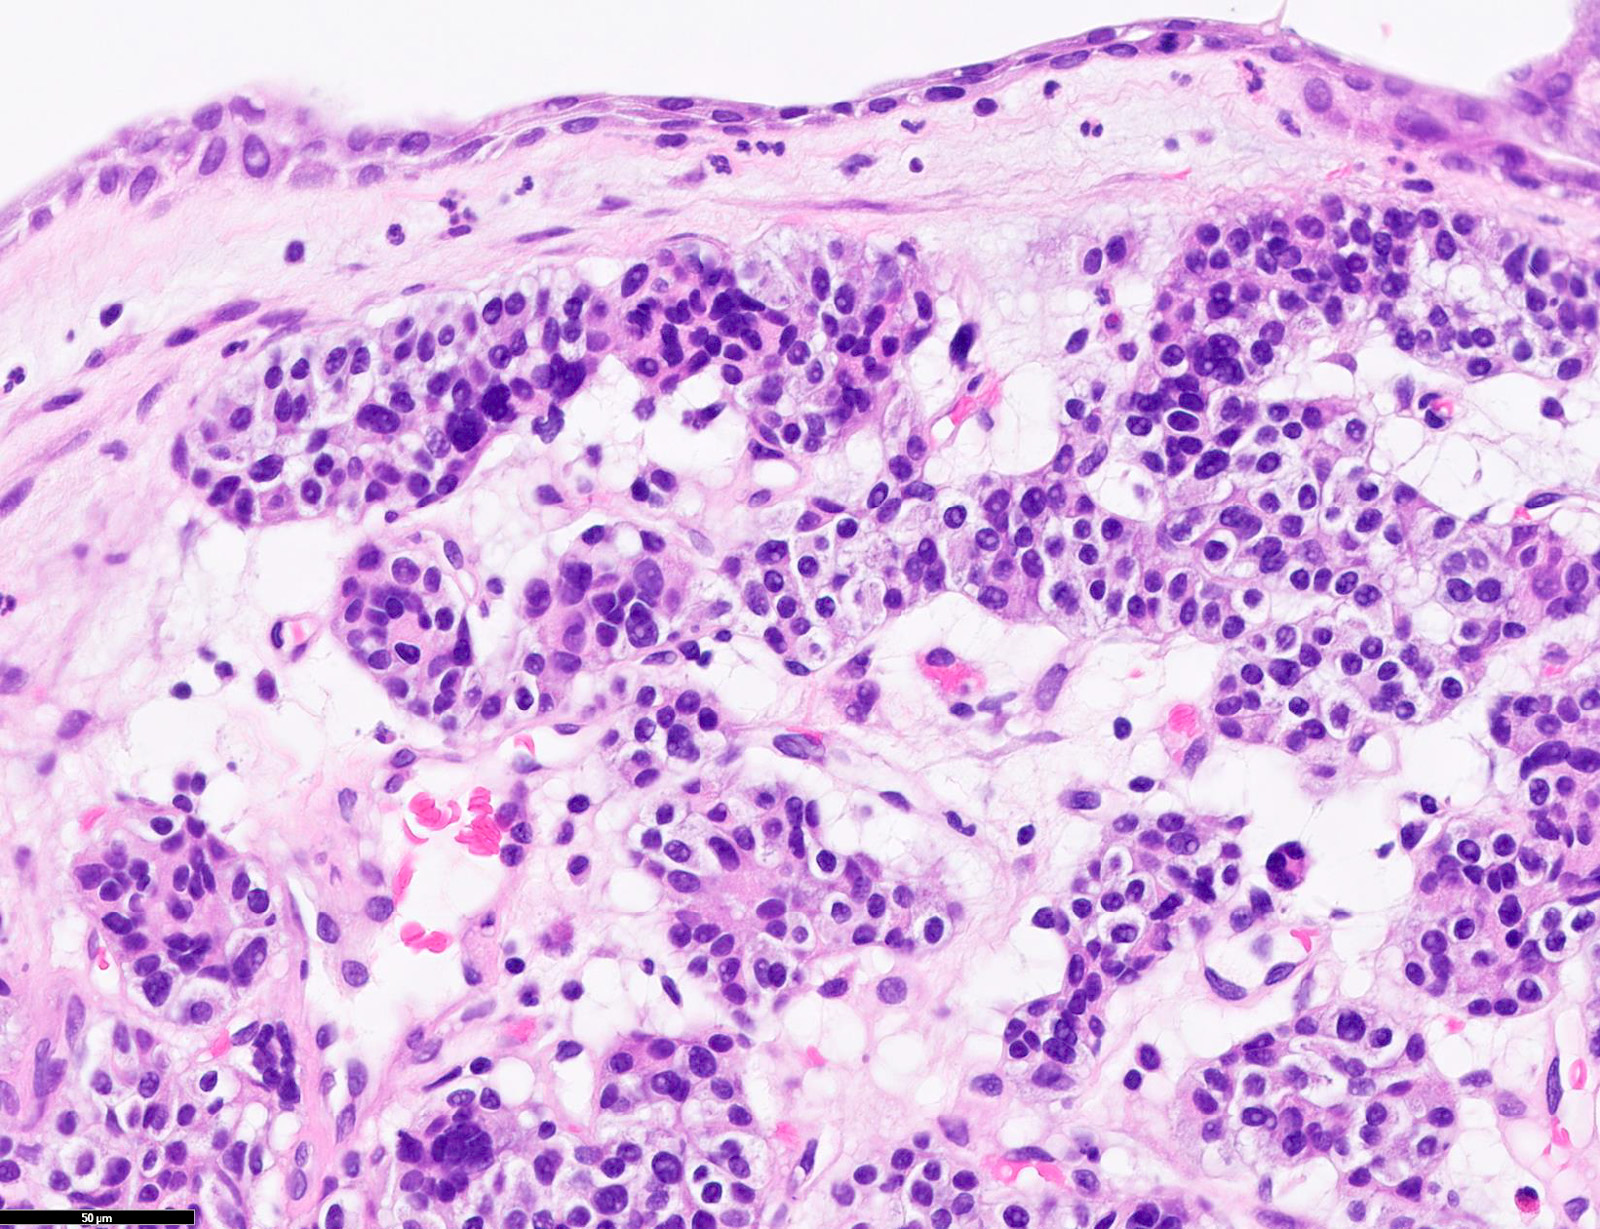

Microscopic (histologic) description

- Diagnostic criteria

- Neuroendocrine tumor with size ≥ 5 mm with < 2 mitoses/2 mm2 and absence of necrosis

- Neuroendocrine growth pattern (organoid, trabecular, rosette formation, nested) or pseudoglandular, follicular and papillary growth

- Tumor cells are uniform with a polygonal shape, round to oval nuclei with salt and pepper chromatin as well as inconspicuous nucleoli and moderate to abundant eosinophilic cytoplasm

- Spindle cells and clear cell features can be seen

- Stroma is fine and highly vascularized; hyalinization, cartilage or bone formation are possible

- Reference: Curr Oncol 2018;25:S86

Microscopic (histologic) images

Contributed by Philippe Joubert, M.D., Ph.D., Jijgee Munkhdelger, M.D., Ph.D. and Andrey Bychkov, M.D., Ph.D.

A. CDX2 is usually negative in the lung and is useful to differentiate from a metastasis of an intestinal origin. The image shows a tumor with a trabecular pattern and pseudorosettes. The stroma is highly vascularized. Tumor cells are monotonous with scant to moderate eosinophilic cytoplasm. Nuclei are round to oval with salt and pepper chromatin and inconspicuous nucleoli. No mitoses are seen. These features are consistent with a typical carcinoid lung tumor.